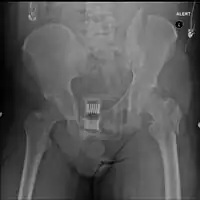

Initial

A high index of suspicion should be held for pelvic injuries in any one with major trauma. The pelvis should be stabilized with a pelvic binder.[13] This can be a purpose made device; however, improvised pelvic binders have also been used around to good effect.[14] Stabilisation of the pelvic ring reduces blood loss from the pelvic vessels and reduced the risk of death.